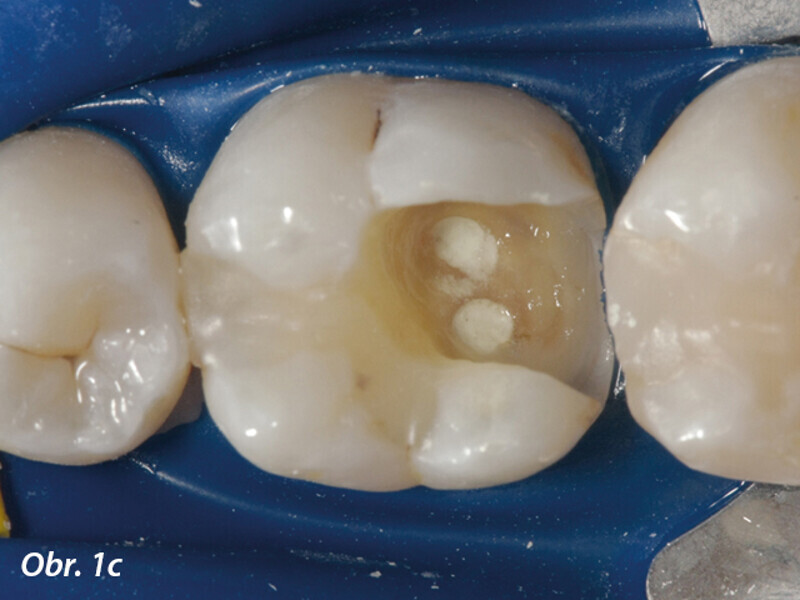

Aplikace MTA s použitím Produit Dentaires (PD) MAP System